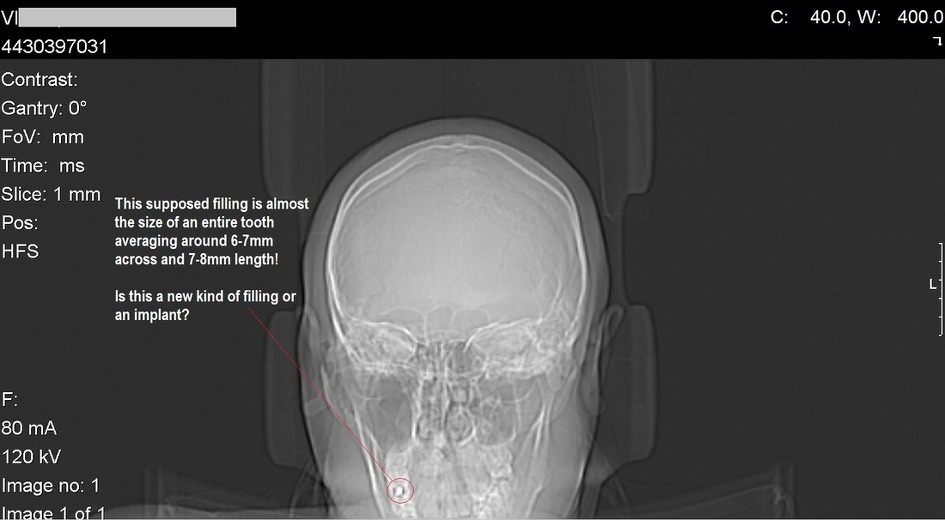

4. 마인드컨트롤 전자파 무기 피해자(TI: TARGETED INDIVIDUALS )들의 신체에 삽입된 칩

저도 뉴욕에 삽니다. 저의 동의없이 저도 TI 인대요..트라우마 기반 mindcontrol 실험대상자입니다. 2008년이래로 제 아들이 전기고문생체실험대상이 되었고, 2008년 이전에는 제 딸이 정신이상으로 정신과적 증상을 가지고 있습니다. 하루종일 기민증과 피곤함을 호소하고요. 저도 왼쪽팔이 마비가 오고, 이유없는 치통과 통증 그리고 건망증을 가지고 있습니다. 치과에 가서 사진을 찍어보니 치아는 이상이 없고요 단지 민감증 이라고만 했습니다. 제 오른다리는 항상 저리고 뜨겁게 달아오르고 가렵고 통증이 동반되고요.

피부가 분홍으로 부풀어 오르고 줄무늬가 생겨납니다. 제가 여기에 증거사진을 가지고 왔는데요.(엑스레이사진을 들어올려보입니다.)

저는 미시건에서 온 레슬리 크로포드라고 합니다. 저는 Bio-technology에 대해서 말씀드리고자 합니다. 여기 제가 안과에서 진료받은 진단과 사진을 가지고 왔습니다.(사진을 보여줍니다.) 안과사진과 두뇌스캔사진을 보여줍니다. 그리고 악관절 임플란트사진을 역시 보여줍니다.